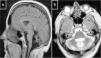

Cerebrotendinous xanthomatosisCX is caused by mutations to the CYP27A1 gene (2q35), which codes for sterol 27-hydroxylase, an enzyme involved in bile acid synthesis.51 Deficiency of this enzyme causes an accumulation of various sterols, including cholestanol, which is observed at high levels in the serum. Neurological symptoms usually appear late in the second decade of life, and comprise epilepsy, ataxia, pyramidal signs, and polyneuropathy. Psychiatric disorders are also common. Prior to onset of neurological symptoms, patients often have diarrhoea, cataracts, and tendon xanthomas; however, 3 patients from 2 different families have been observed not to display this sign, leading to diagnostic delays.52,53 MRI sometimes reveals hyperintensities in the dentate nuclei, enlarged cranial sinuses, and cervical spinal cord atrophy (Fig. 2B). Administration of chenodeoxycholic acid slows the progression of CX.

MR images of treatable hereditary ataxias secondary to metabolic disorders. A) Axial T2-weighted sequence from a patient with Wilson disease, showing periaqueductal hyperintensity, contrasting with hypointensity in the mammillary bodies, red nuclei, and substantia nigra, forming the “panda sign.” B) Sagittal T1-weighted sequence showing enlarged cranial sinuses and spinal cord atrophy in a patient with cerebrotendinous xanthomatosis. C) T2-weighted sequence showing atrophy in the cortex, corpus callosum, brainstem, and cerebellar vermis in a patient with Niemann-Pick disease type C.

This condition is caused by mutations to the NPC1 gene (18q11.2), coding for a transmembrane protein (90% of cases), or NPC2 (14q24.3), coding for an intralysosomal protein (10%). Deficiencies of these proteins distort the trafficking of cholesterol, sphingosine, and glycolipids, which accumulate in the lysosomes, leading to cell death.54 Clinical phenotypes vary according to age of onset: the neonatal form is fatal; the early childhood form causes hypotonia and psychomotor retardation; the late childhood form causes poor coordination, gait and language acquisition disorders, and gelastic cataplexy; the juvenile form causes ataxia, epilepsy, cataplexy, and poor school performance; and the adult form causes psychiatric disorders, ataxia, dystonia, and dementia.55 New massively parallel sequencing techniques have enabled more late-onset cases to be identified.56 Vertical gaze palsy is usually a symptom of the latter 3 forms. Patients often have a history of splenomegaly and prolonged neonatal jaundice. MRI scans reveal brain, cerebellar, and brainstem atrophy (Fig. 2C). Chitotriosidase in macrophages and CCL18 in the plasma do not always display high levels of activity. Filipin staining of fibroblast cultures reveals an accumulation of cholesterol. Administration of miglustat may improve disease progression.

Wilson diseaseWilson disease is caused by mutations to the ATP7B gene (13q14.3), which codes for an ATPase involved in transporting copper across the Golgi apparatus in hepatocytes.57 It can present in different forms, including fulminant hepatitis, psychosis, and neurological disorders (tremor, dystonia, akinetic-rigid syndrome, and occasionally ataxia). Most patients with neurological symptoms display the Kayser-Fleischer ring.58 MRI findings (Fig. 2A) vary greatly, as has previously been described.59 Laboratory testing shows low blood ceruloplasmin and copper levels and increased urine copper levels. The habitual treatment comprises D-penicillamine and trientine as chelants, as well as tetrathiomolybdate and zinc sulfate.59